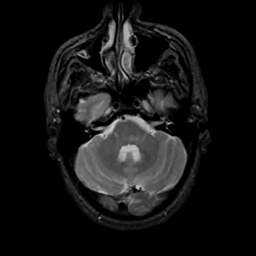

MR Study #8, March 31, 1991 -- Slice #12